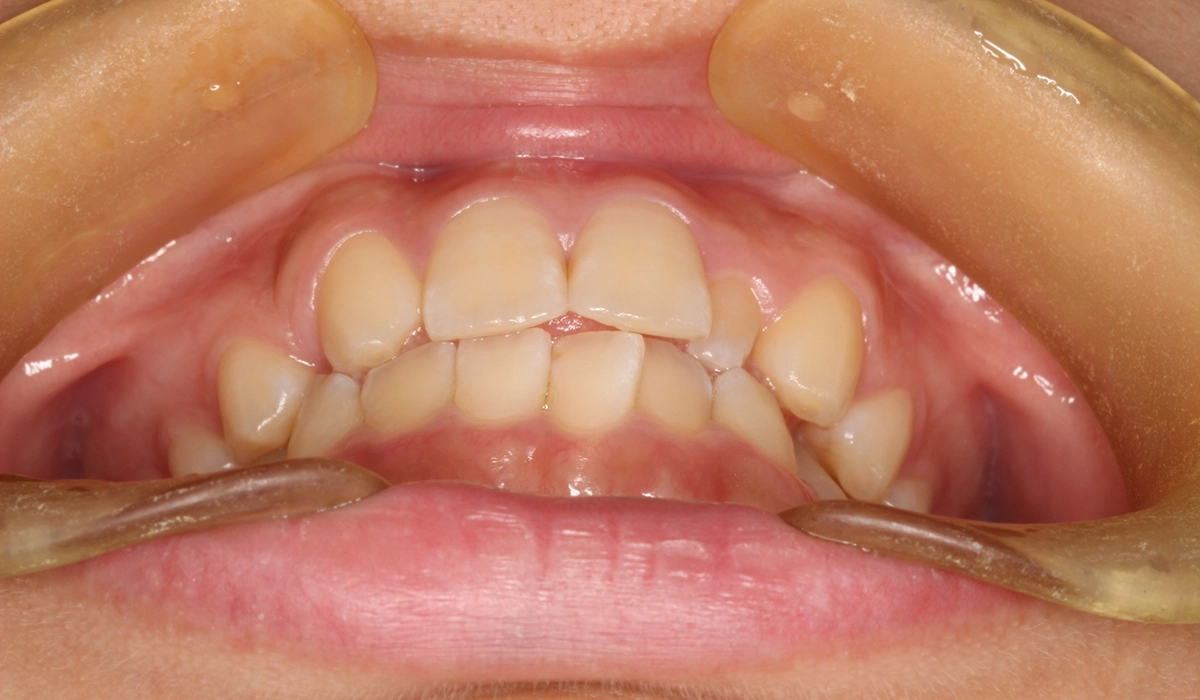

術前:正面

術後:正面